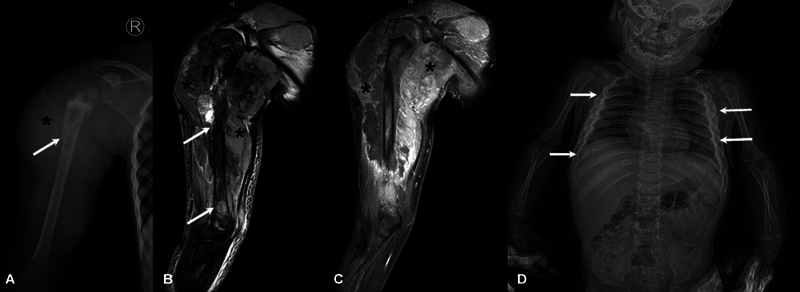

慢性非感染性骨髓炎或慢性非细菌性骨髓炎(CNO),也称为慢性复发性多灶性骨髓炎,是一种主要影响儿童年龄组的自身炎症性骨疾病。目前,该病的诊断主要基于临床、实验室和影像学特征。影像学在CNO的诊断和随访中起着至关重要的作用,全身磁共振成像(WBMRI)是主要方式。x光片有助于排除常见的鉴别诊断,如感染和恶性肿瘤。WBMRI有助于疾病检测和鉴别诊断的排除,识别额外的病变,并在确定骨骼受累模式方面发挥作用,有助于预测和分级。最近对WBMRI上特定形态和分布模式的认识越来越多地允许仅通过成像对该实体进行预先诊断。这也有助于在随访中评估对治疗的反应。本文旨在总结影像学在CNO评估中的作用,特别强调WBMRI在其评估中的作用。

Chronic noninfectious osteomyelitis or chronic nonbacterial osteomyelitis (CNO), also known as chronic recurrent multifocal osteomyelitis, is an autoinflammatory bone disorder primarily affecting the pediatric age group. Currently, it is diagnosed on the basis of clinical, laboratory, and imaging features. Imaging plays a crucial role in the diagnosis and follow-up of CNO with whole body magnetic resonance imaging (WBMRI) being the main modality. Radiographs assist in exclusion of common differential diagnoses like infections and malignancy. WBMRI aids in disease detection and exclusion of differential diagnoses, identifies additional lesions, and has a role in ascertaining the pattern of bony involvement which helps with prognostication and grading. Recent recognition of specific morphological and distribution patterns on WBMRI is increasingly allowing an upfront diagnosis of this entity to be made on imaging alone. It is also helpful for assessment of response to therapy during follow-up. This review aims to summarize the role of imaging in the evaluation of CNO, with special emphasis on WBMRI in its assessment.